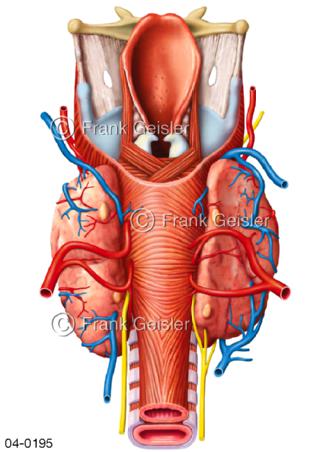

Bildergalerie Topografie Organe

Bilder zur topografischen Anatomie, die Lage der Organe und die Strukturen nach ihren räumlichen Lagebeziehungen zueinander, Übersicht der inneren Organe im Kopf und im Rumpf, Topografie der Organe im Brustraum (Thorax) und im Bauchraum (Abdomen)